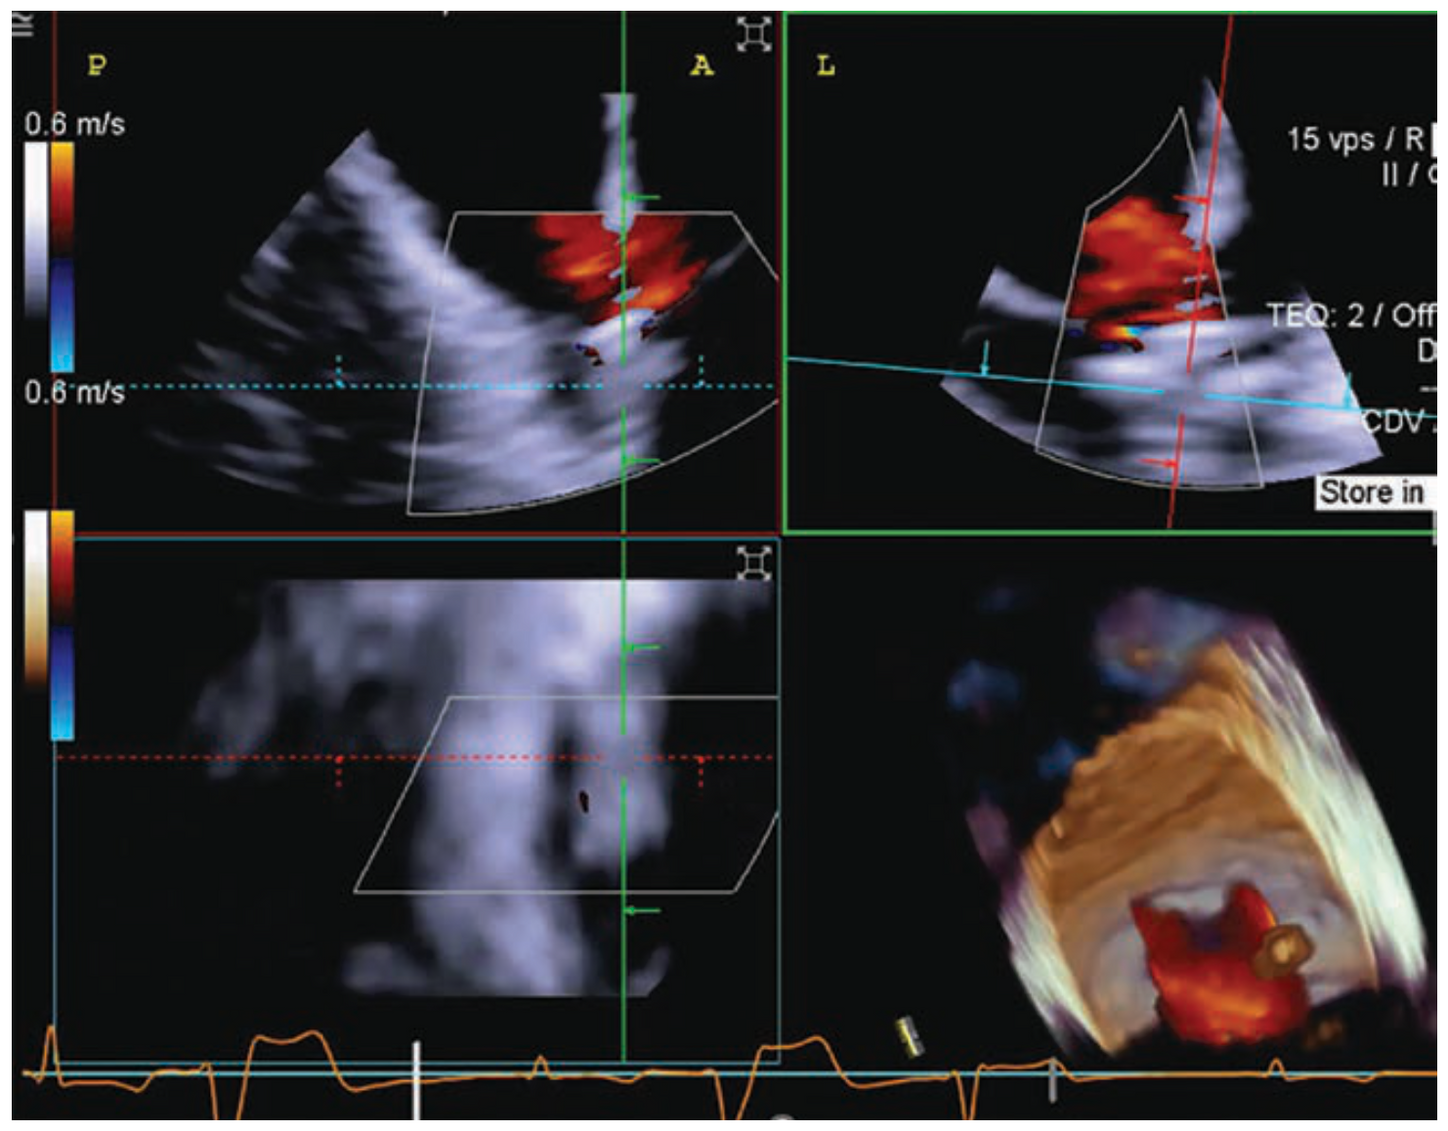

LAA Ostium 3D Calipers

WatchmanTM* device with 3D Calipers

WatchmanTM* MPR sweep

MPR sweep of WatchmanTM* device